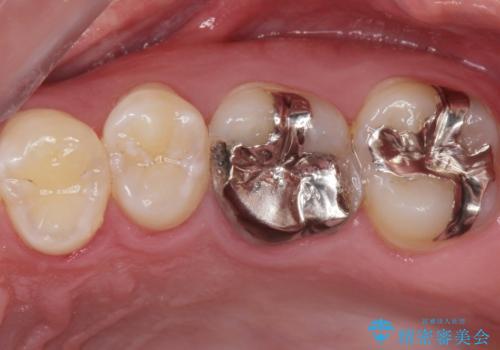

口を開けたら銀が目立つのが気になる。

- 銀が目立つので白くしたいとの事で来院。

銀の詰め物を拡大鏡下で取り除き、う蝕がないことを確認してから

ZrCrの被せ物で治療を行いました。

また、一つ手前の歯に小さな虫歯があったため

e-maxインレーでの治療を行いました。

銀の詰め物の範囲が大きいほど

やりかえをする時、セラミックの詰め物だと割れるリスクがあるため

ZrCrの被せ物のご案内をする事があります。